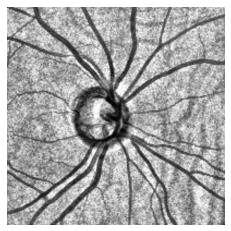

Fairness in artificial intelligence models has gained significantly more attention in recent years, especially in the area of medicine, as fairness in medical models is critical to people's well-being and lives. High-quality medical fairness datasets are needed to promote fairness learning research. Existing medical fairness datasets are all for classification tasks, and no fairness datasets are available for medical segmentation, while medical segmentation is an equally important clinical task as classifications, which can provide detailed spatial information on organ abnormalities ready to be assessed by clinicians. In this paper, we propose the first fairness dataset for medical segmentation named Harvard-FairSeg with 10,000 subject samples. In addition, we propose a fair error-bound scaling approach to reweight the loss function with the upper error-bound in each identity group, using the segment anything model (SAM). We anticipate that the segmentation performance equity can be improved by explicitly tackling the hard cases with high training errors in each identity group. To facilitate fair comparisons, we utilize a novel equity-scaled segmentation performance metric to compare segmentation metrics in the context of fairness, such as the equity-scaled Dice coefficient. Through comprehensive experiments, we demonstrate that our fair error-bound scaling approach either has superior or comparable fairness performance to the state-of-the-art fairness learning models. The dataset and code are publicly accessible via https://ophai.hms.harvard.edu/harvard-fairseg10k.